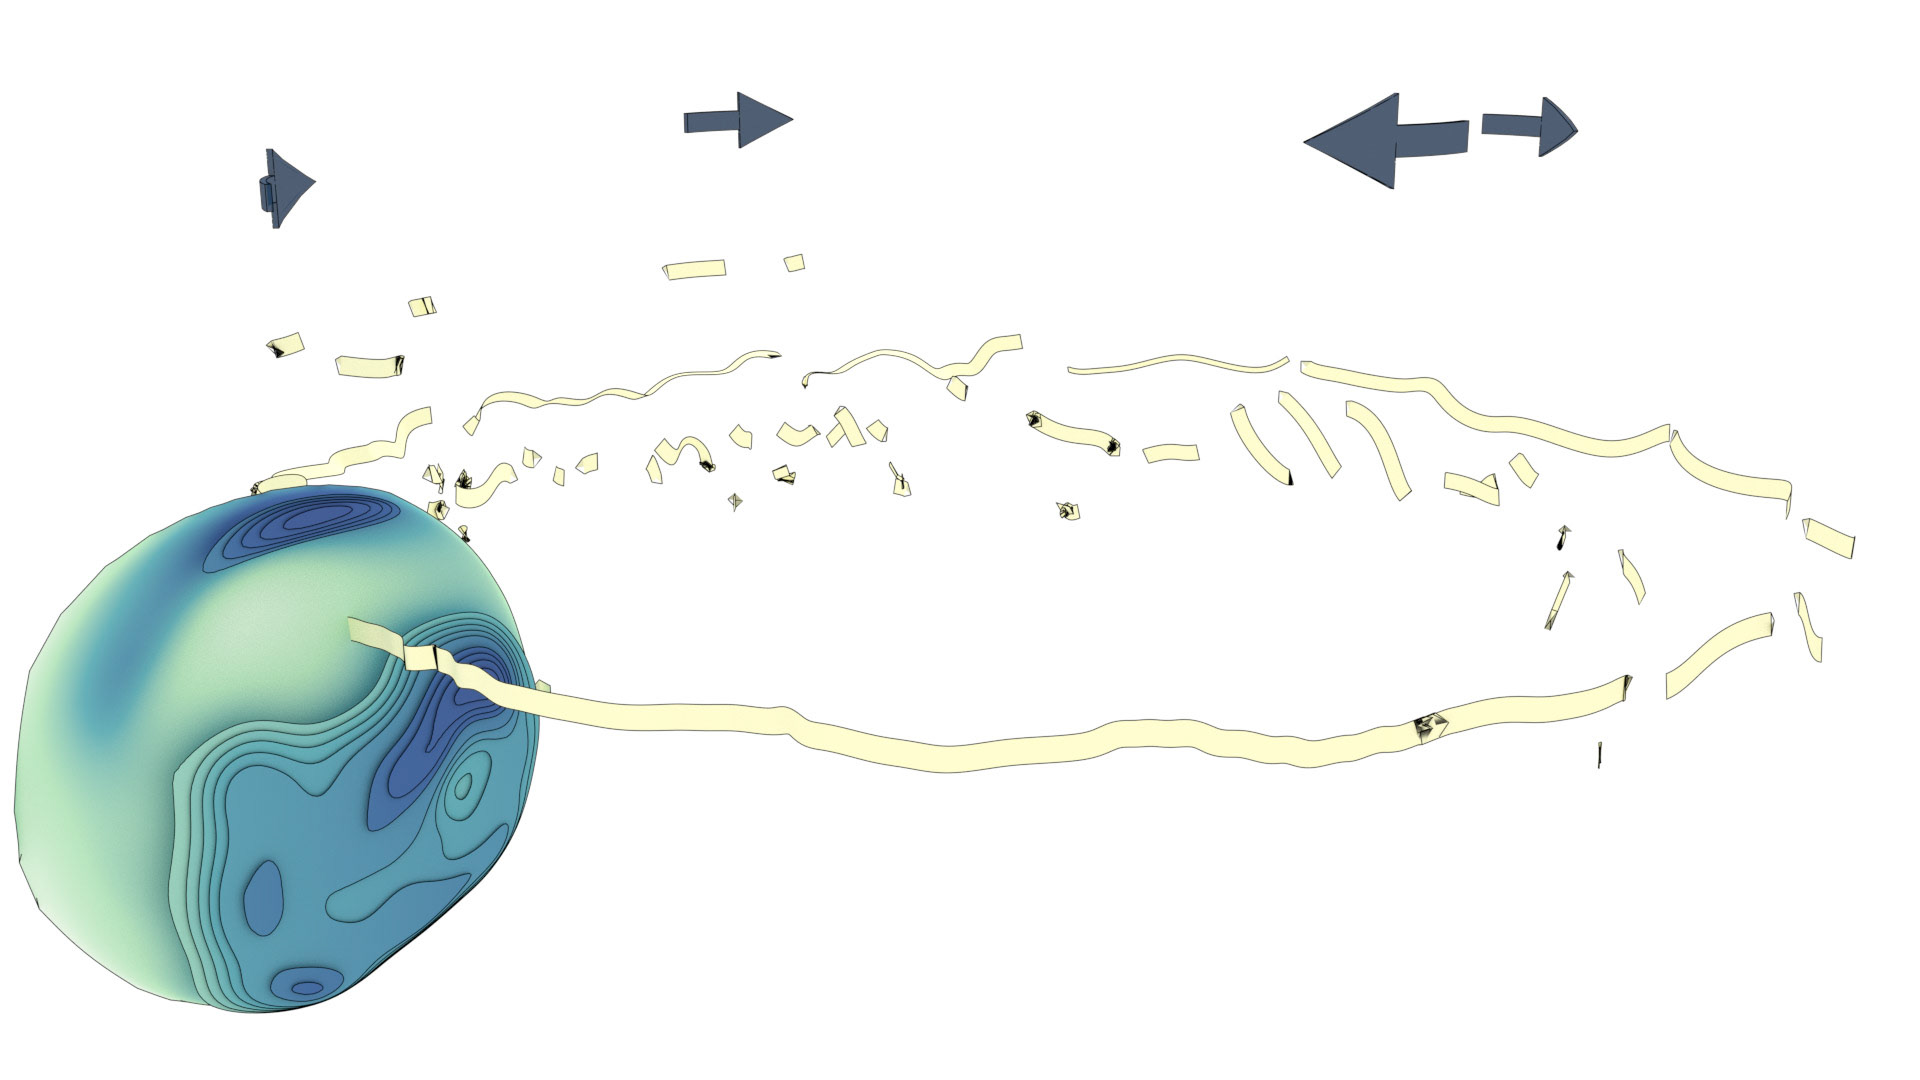

An ongoing collaboration with the Biomedical Simulation Lab (BSL), University of Toronto. In my role, I develop concept sketches and renderings that are then implemented algorithmically. The overall approach is to show turbulent flow visualizations without animation my mapping the transitions among states to carousel that corresponds to the cardiac cycle.